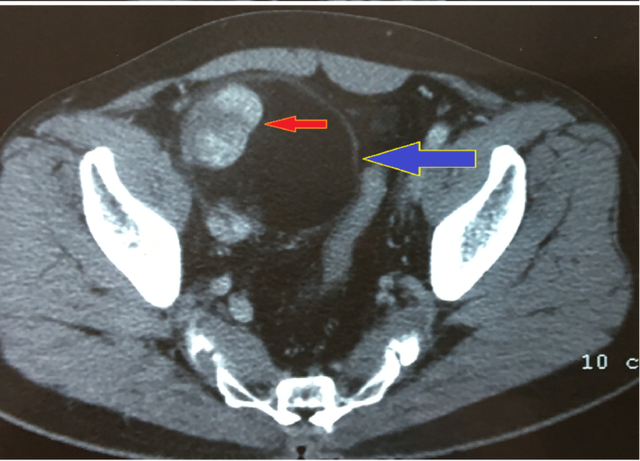

Các kết quả kiểm tra hình ảnh siêu âm tim tại bệnh viện ghi nhận, vùng trung thất của bệnh nhân có khối máu tụ, chèn ép tim, nguy cơ đe dọa trực tiếp đến sinh mạng bệnh nhi. Một lần nữa, sinh mạng cháu bé lại lâm nguy, sau cuộc hội chẩn toàn bệnh viện, các bác sĩ quyết định thực hiện cuộc mổ lần thứ 2 lấy khối máu tụ, đồng thời đánh giá tổn thương tim. Sau mổ, mạch, huyết áp bé ổn định lại, bênh nhi tạm thời qua cơn nguy kịch. Hiện cháu đang được các bác sĩ chăm sóc, hồi sức tích cực.